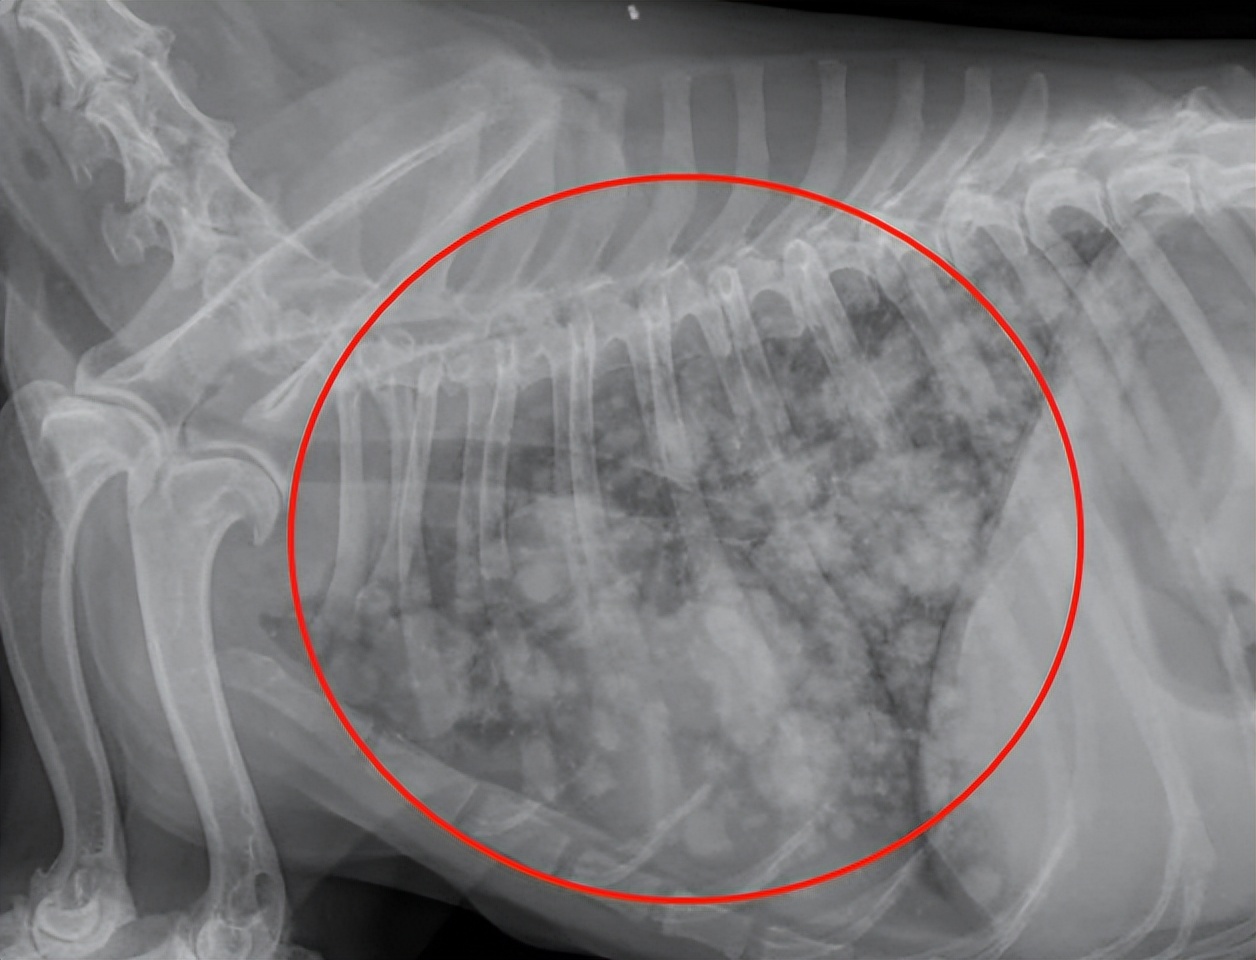

而乳腺肿瘤一旦恶化,就会使得皮肤裂开,肿瘤内部出现破裂。只要没有给做切除乳腺癌的手术,那么生长得特快的肿瘤就很有可能会出现破裂,甚至有些狗狗总是去舔乳房周围的皮肤的话还会加快破裂的速度。肿瘤通常扩散到局部淋巴结和肺部。

希望每个主人带狗狗检查时不要呈现这样的照片!下面这张图就是乳腺癌肺部转移X光照片。